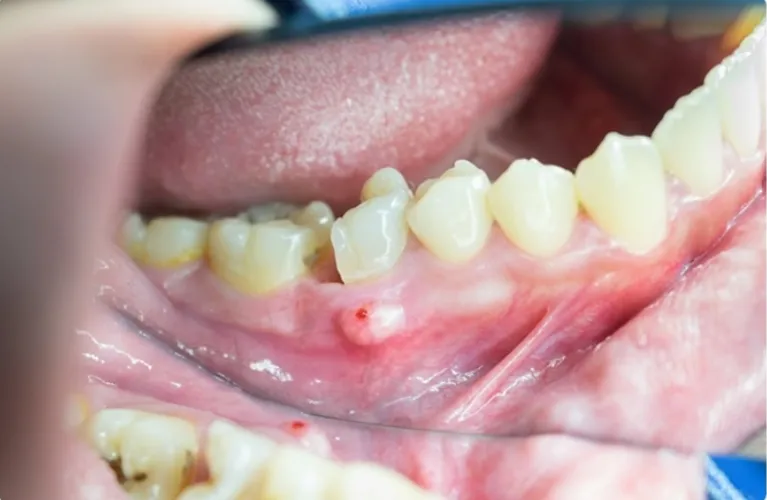

Infection or abscess

When a tooth infection is severe and not treatable with antibiotics or a root canal, extraction may be necessary.